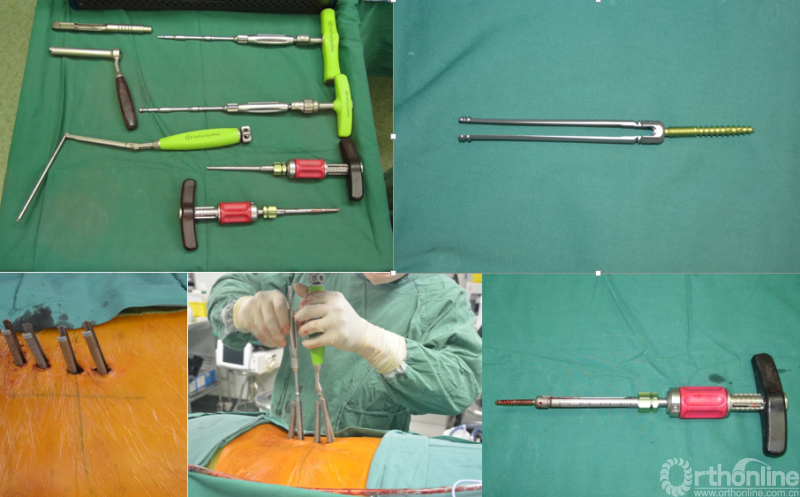

问题1:在进行脊柱全椎体切除时,以往的文献和操作中都是应用线锯来进行椎间盘或椎体的切开,进而全椎体切除。但是临床操作时不难发现,从前往后进行肿瘤切除时,在前方不好控制线锯的位置,常常出现操作位置有偏差的问题,甚至有时候会进入到一部分肿瘤当中,造成肿瘤范围的不必要扩大,影响手术边界及患者的预后。

汤小东教授经验:通过不断对操作中遇到的问题进行总结,他发现使用一个空心钉预先打入待切除的椎间盘或椎体中,然后通过空心钉导入线锯,这样线锯的位置就可以准确控制,进而很好地切除肿瘤椎体。

为进一步减少创伤,获得更好的综合疗效。骨采用经皮内固定的微创杂交技术,暨经皮内固定结合小切口分离手术,手术失血900ml,术后7天出院。

术中资料